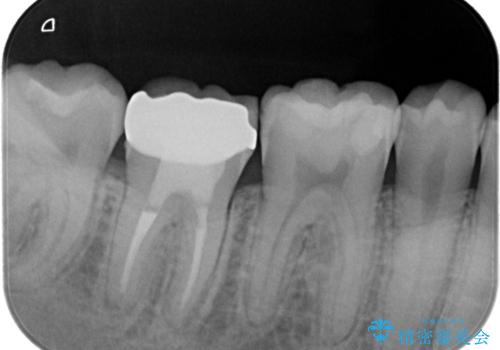

- 奥歯がズーンと痛いことを主訴に来院されました。

根管治療時に穿孔部位を認め、MTAにて修復し、分岐部の歯周ポケットおよび骨欠損に対しては、再生治療を行うことで、正常な歯周状態の獲得ができました。